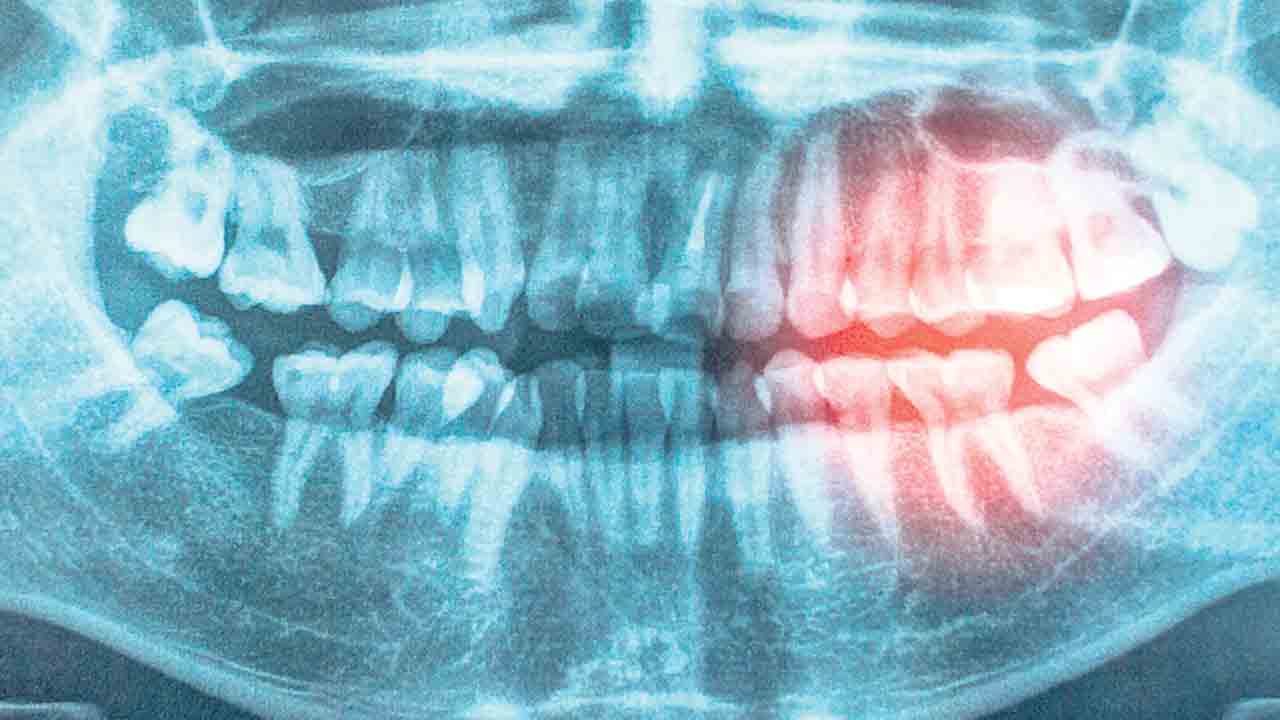

చిగుళ్ల వ్యాధులు అథెరోస్లెరోటిక్ కార్డియో వాస్క్యులర్ డిసీజ్ (ధమనులు మూసుకుపోవడం) వల్ల కలిగే గుండె సమస్యలు పీరియాంటల్ వ్యాధితో దగ్గర సంబంధం కలిగి ఉన్నాయని తాజా పరిశోధన నివేదికలో స్పష్టం చేశారు. ఇందుకు గల కారణాలను విశ్లేషించారు. దెబ్బ తిన్న చిగుళ్ల ద్వారా శరీరంలోకి బ్యాక్టీరియా ప్రవేశిస్తుందని గుర్తించారు. చిగుళ్లు, నోటి ఆరోగ్యం దెబ్బ తింటే ప్రమాదకరమైన రక్తనాళాల వాపు సమస్య వస్తుందని పేర్కొన్నారు. పొగ తాగడం, వృద్ధాప్యం, ఊబకాయం కారణంగా చిగుళ్ల వ్యాధులు, ధమనులు మూసుకుపోవడం వంటి సమస్యలు తలెత్తుతాయని వివరించారు.